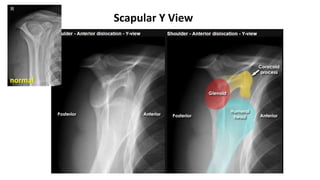

Routine films : AP view , Scapular Y view , Axillary view (ไม่นิยม)

finding : humeral head comes to lie anteromedial

1. Subcoracoid (m/c)

2. Subglenoid

3. Subclavicular

4. Intrathoracic

4 subtype

70 % 30 %

rare rare

AP View

normal

Scapular Y View